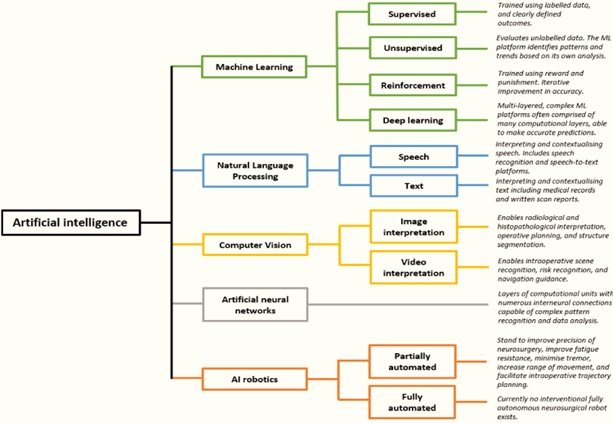

Human-machine intelligence (AI) One of the current uses of artificial intelligence (AI) is machine learning (ML), a branch of computer science that focuses on building intelligent machines that mimic human behavior. ML is based on the notion that we should give machines access to data so they can learn on their own. DL is a subfield of ML. While deep learning is more akin to animal vision, machine learning is more like human vision. Convolutional Neural Network (CNN) is a new method for image analysis using deep learning. Computer assisted diagnostic (CAD) technologies process digital pictures to highlight certain noticeable disorders to help radiologists or other medical practitioners.11 As displayed in Figure 1.

Figure 2 displays the five major subdomains of artificial intelligence. There are several possible clinical uses for each subdomain of AI in brain tumor surgery. There are many more subfields within AI, hence this diagram is not all-inclusive. In12 the dependent variable (the target) and the independent variable (a collection of predictors) make up supervised learning. These variables are used to create a function that maps inputs to intended outputs. The model is trained repeatedly until it reaches a high degree of accuracy on the training set. kNN, logistic regression, decision trees, random forests, regression, and so on are a few instances of supervised learning. There won't be any target variable to forecast in unsupervised learning. Examples of unsupervised learning include k-means, apriori algorithms, and others. The machine is placed in an environment where it continuously educates itself through trial and error in reinforcement learning. In this case, the computer attempts to get the knowledge necessary to make accurate decisions by learning from its prior experiences. Markov decision process serves as one illustration of reinforcement learning (Figure 3).13

Figure 2 The five key subdomains of Artificial intelligence.12